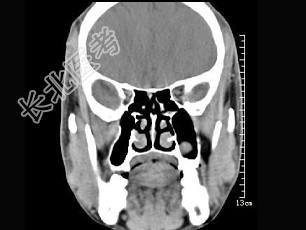

- 单项选择题男,7岁, 无明显症状,CT如图所示, 最可能的诊断是 ( )

A、上颌窦淋巴瘤

B、上颌窦炎

C、上颌窦黏膜下囊肿

D、上颌窦乳头状瘤

E、鼻炎及副鼻窦黏膜下囊肿